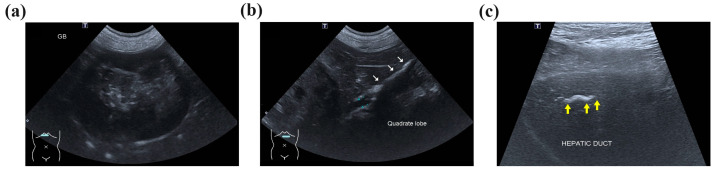

Abdominal radiography revealed radiopaque material suggestive of cholelithiasis in the liver, GB, and CBD area. Ultrasonography (US) showed a mucocele in the GB (Figure 1a) and hepatolithiasis in the left medial, quadrate, and right liver lobes and the GB (Figure 1b,c). The intrahepatic bile duct was dilated with a diameter of approximately 3.3 mm. Distal CBD dilatation was not observed.